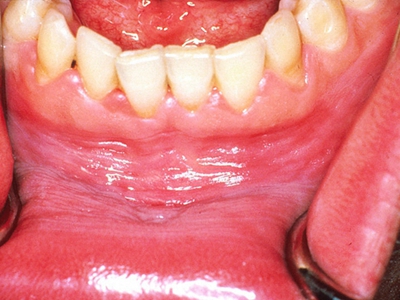

牙龈炎是发生于牙龈组织的炎症,患者可出现牙龈出血伴肿胀、发红、正常形态改变和偶尔不适等症状。本病主要由口腔卫生状况差导致,包括口腔不洁、牙菌斑等,诊断依据临床检查,治疗包括专业牙齿清洁和加强家庭口腔卫生。

牙龈炎可先引起牙齿与牙龈之间的沟(龈沟)加深,然后牙龈充血,炎症围绕一个或多个牙齿,伴牙龈乳头肿胀和易出血。一般无痛,可自行消退,也可维持轻度炎症数年。

牙龈炎患者可通过改善口腔卫生控制疾病,同时使用抗菌漱口液,如复方氯己定含漱液,并进行彻底的洁治处理。必要时,重新修整修复体的不良外形,并祛除局部刺激因素。